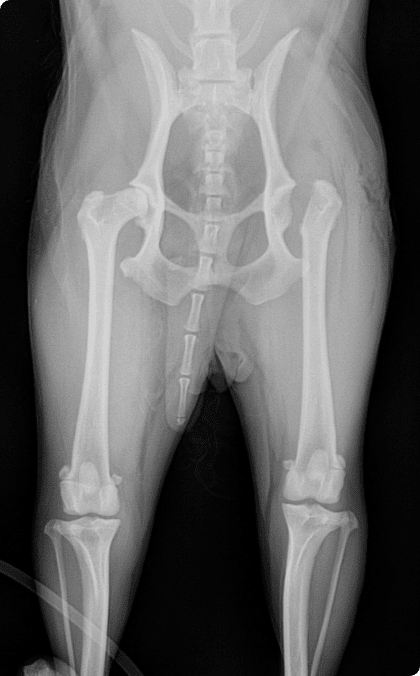

선천적 탈구부터 퇴행성 관절질환까지 다양한 고관절 문제를

통증은 최소화하고 재발 방지와 기능 회복에 집중합니다.

골절은 반려동물에서 흔히 발생하는 정형외과 질환으로

단순 골절부터 복합 골절까지 형태와 정도가 다양하며

주변 근육·혈관·신경 손상이 동반될 수 있어

신속하고 정밀한 치료가 필요함.